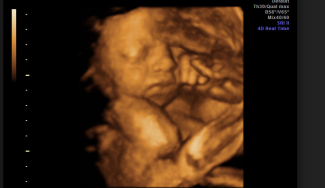

- 229 nenarodených detí bolo zabitých pri neskorých potratoch po 24. týždni tehotenstva.